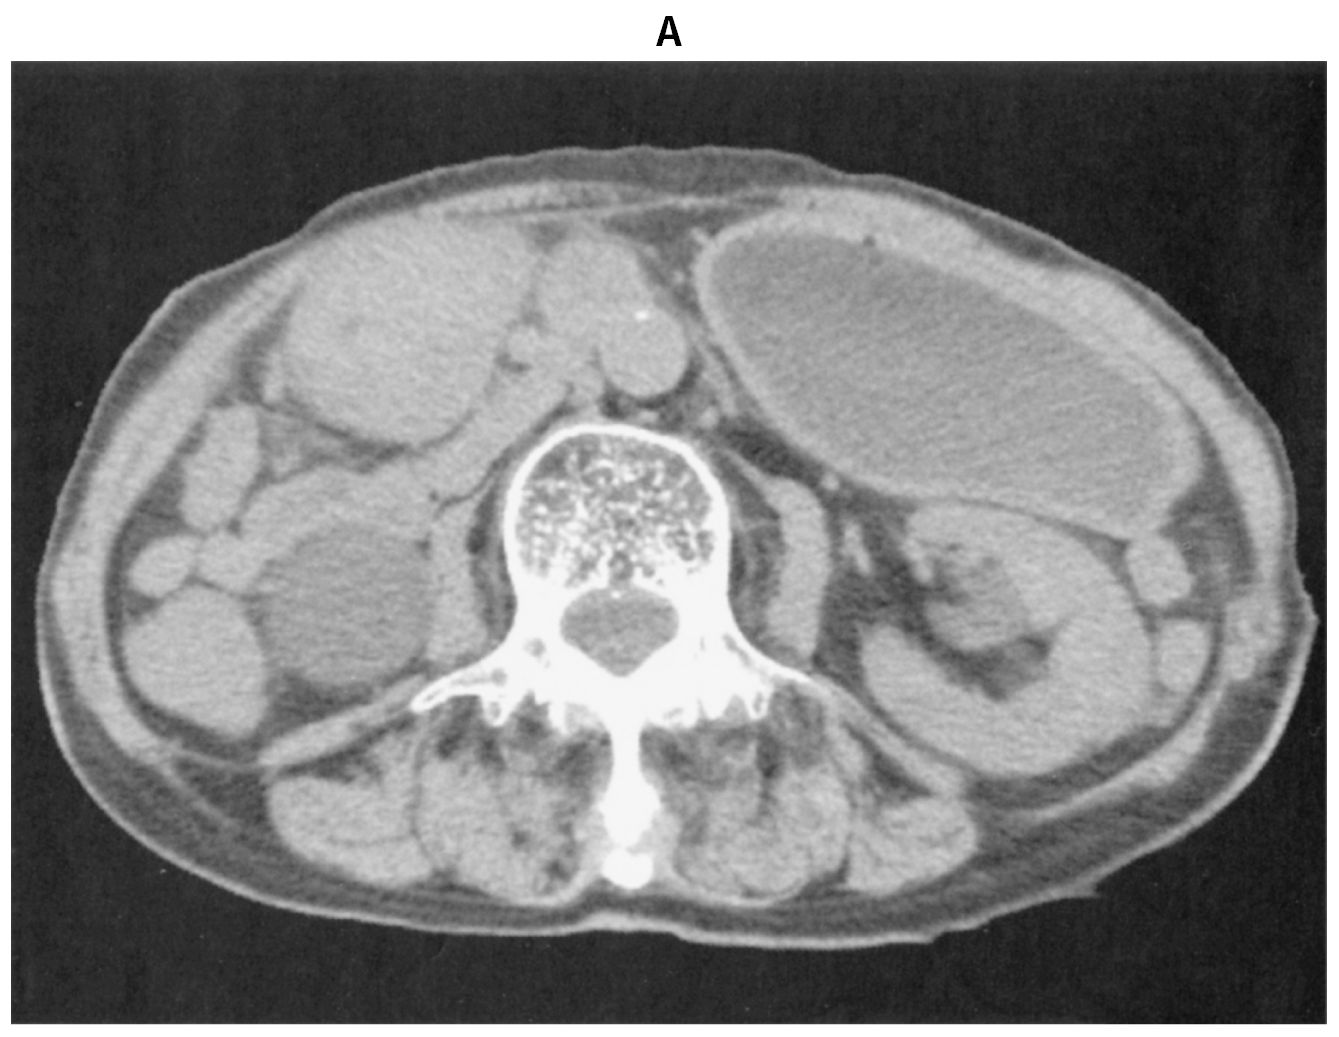

88歳の女性。呼吸困難を主訴に救急車で搬入された。3か月前から心窩部痛があり,2か月前には悪心で食事が摂れなくなり,3週間前から嘔吐を繰り返すようになった。睡眠中に嘔吐し,呼吸困難が出現したため家族が救急車を要請した。喫煙歴と飲酒歴はない。意識は清明。身長148cm,体重36kg。1か月で6kg体重が減少した。体温36.2℃。心拍数108/分,整。血圧98/48mmHg。呼吸数12/分。SpO2 94%(マスク5L/分 酸素投与下)。呼吸音は前胸部右側で減弱し,coarse cracklesを聴取する。腹部は膨隆し,圧痛を認める。尿所見:蛋白(-),糖(-),ケトン体2+,潜血(-)。血液所見:赤血球418万,Hb 11.9 g/dL,Ht 38%,白血球5,500,血小板30万。血液生化学所見:総蛋白6.4g/dL,アルブミン2.8g/dL,総ビリルビン0.5mg/dL,AST 26U/L,ALT 18U/L,LD 202U/L(基準124~222),ALP 110U/L(基準38~113),尿素窒素28mg/dL,クレアチニン1.4mg/dL,血糖88mg/dL,Na 132mEq/L,K 4.6mEq/L,Cl 98mEq/L,Ca 8.8mg/dL,P 2.7mg/dL,CEA 18.6ng/mL(基準5以下),CA19-9 36U/mL(基準37以下)。CRP 3.0mg/dL。腹部単純CT(A)(B)を下に示す。気管内吸引で食物残渣を多量に認め,その後低酸素血症は改善した。2週間後に開腹手術を行うことにした。低栄養に対して,栄養サポートチーム〈NST〉に介入依頼をした。